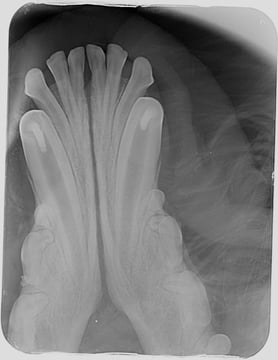

Radiography is important to confirm the position and degree of resorption of the deciduous teeth to be extracted. Like all deciduous dentition, the tooth roots are extremely long in comparison to the length of the crowns. This is especially dramatic in deciduous canine and incisor teeth: the roots of these teeth could be as much as four to six times the length of the crown. For better visualisation, an open technique is advisable. The complete extraction of the deciduous canines is important in interceptive orthodontic procedures, as retained root remnants could still affect the position of the permanent succedaneous canine teeth. Post-operative radiography to confirm complete extraction in these cases is therefore important.